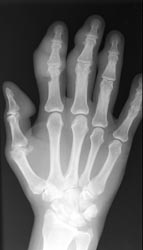

While all of the compartments of the hand and wrist are susceptible, the carpometacarpal

and intercarpal joints are the most frequently involved. Asymmetric distribution

is characteristic of gouty arthritis.

Radiographic Appearance:

Periarticular soft tissue swelling may be the first radiographic sign of an

acute gouty attack. Soft tissue sodium urate deposits can occur with chronic

gout which creates a dense mass called a tophus that can occasionally contain

calcifications. This distribution is random and is usually seen on the dorsal

surfaces. Osseous erosions are periarticular with sharp sclerotic margins

and an asymmetric distribution. Overhanging edges with a well-defined osseous

shelf at the erosive site can sometimes be seen. Loss of normal bone mineralization

is not a characteristic finding of gout and if present, the osteoporotic findings

are mild. Joint space narrowing does not usually present except in more advanced

stages.